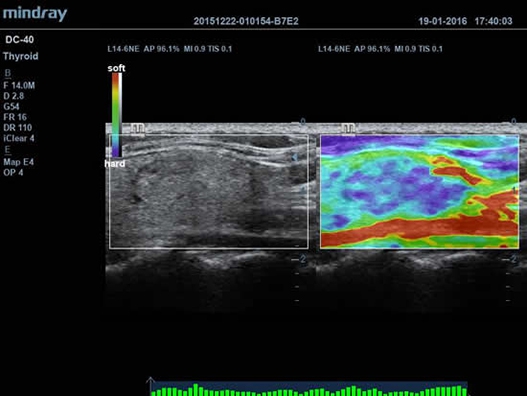

• Функция эластографии Natural Touch позволяет проводить эластографические исследования.

• iClear™ - технология, подавляющая помехи (артефакты) и обеспечивающая получений четких ультразвуковых изображений высокого разрешения для 2D-режима;

• iBeam™ - режим многолучевого компаундинга;